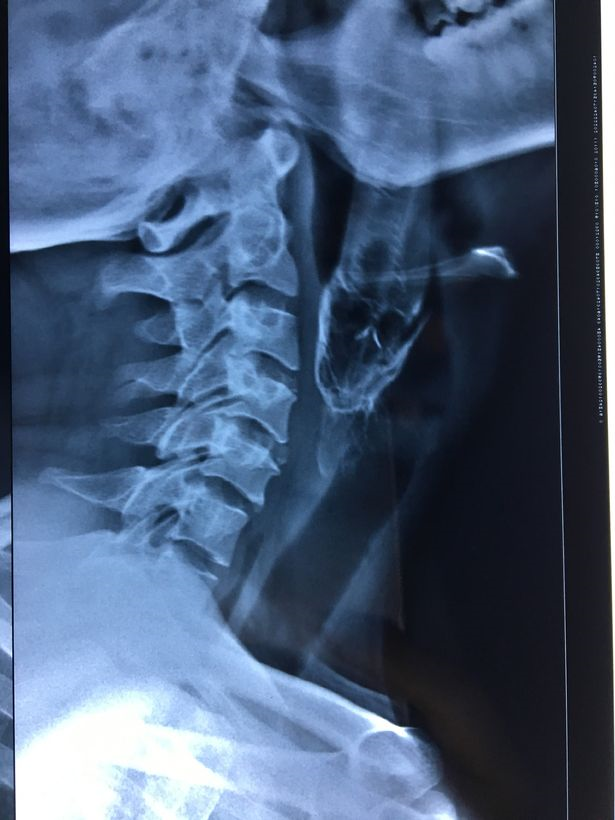

Kemudian dia dipindahkan ke Hospital Appolo di Bhuwaneshwar yang terletak kira-kira 200 kilometer dari kampungnya di Podadhia dan doktor di sana berjaya mengeluarkan ikan itu menggunakan alat penyepit khas.

Pemeriksaan lanjut mendapati tekak lelaki itu mengalami luka teruk akibat terkena sirip tajam ikan berkenaan.

Wakil hospital itu, Dr Sanjeev Gupta berkata, pada awalnya, beliau hanya nampak ekor ikan tersebut yang berukuran 10 sentimeter.

"Kami membawanya ke dewan bedah sebelu memulakan proses mengeluarkan ikan tersebut menggunakan alat khas," katanya menurut laporan portal Mirror.